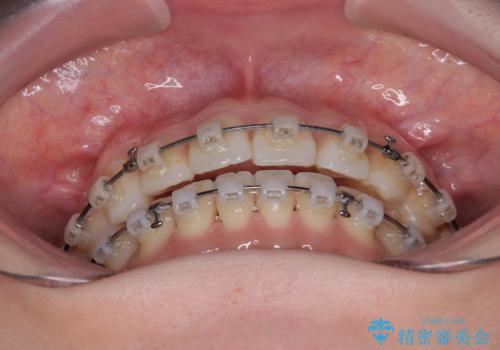

- クリアブラケット

- 1年6ヶ月

補助装置を用いて上顎臼歯を後方移動させ、歯列を整えながら前歯部の接触を図ることとしました。

舌の突出癖改善のためのトレーニングを指導しながら、ワイヤー装置にて矯正治療を行うこととしました。

舌のトレーニングは不十分でしたが、1年半ほどで治療を終えることができました。